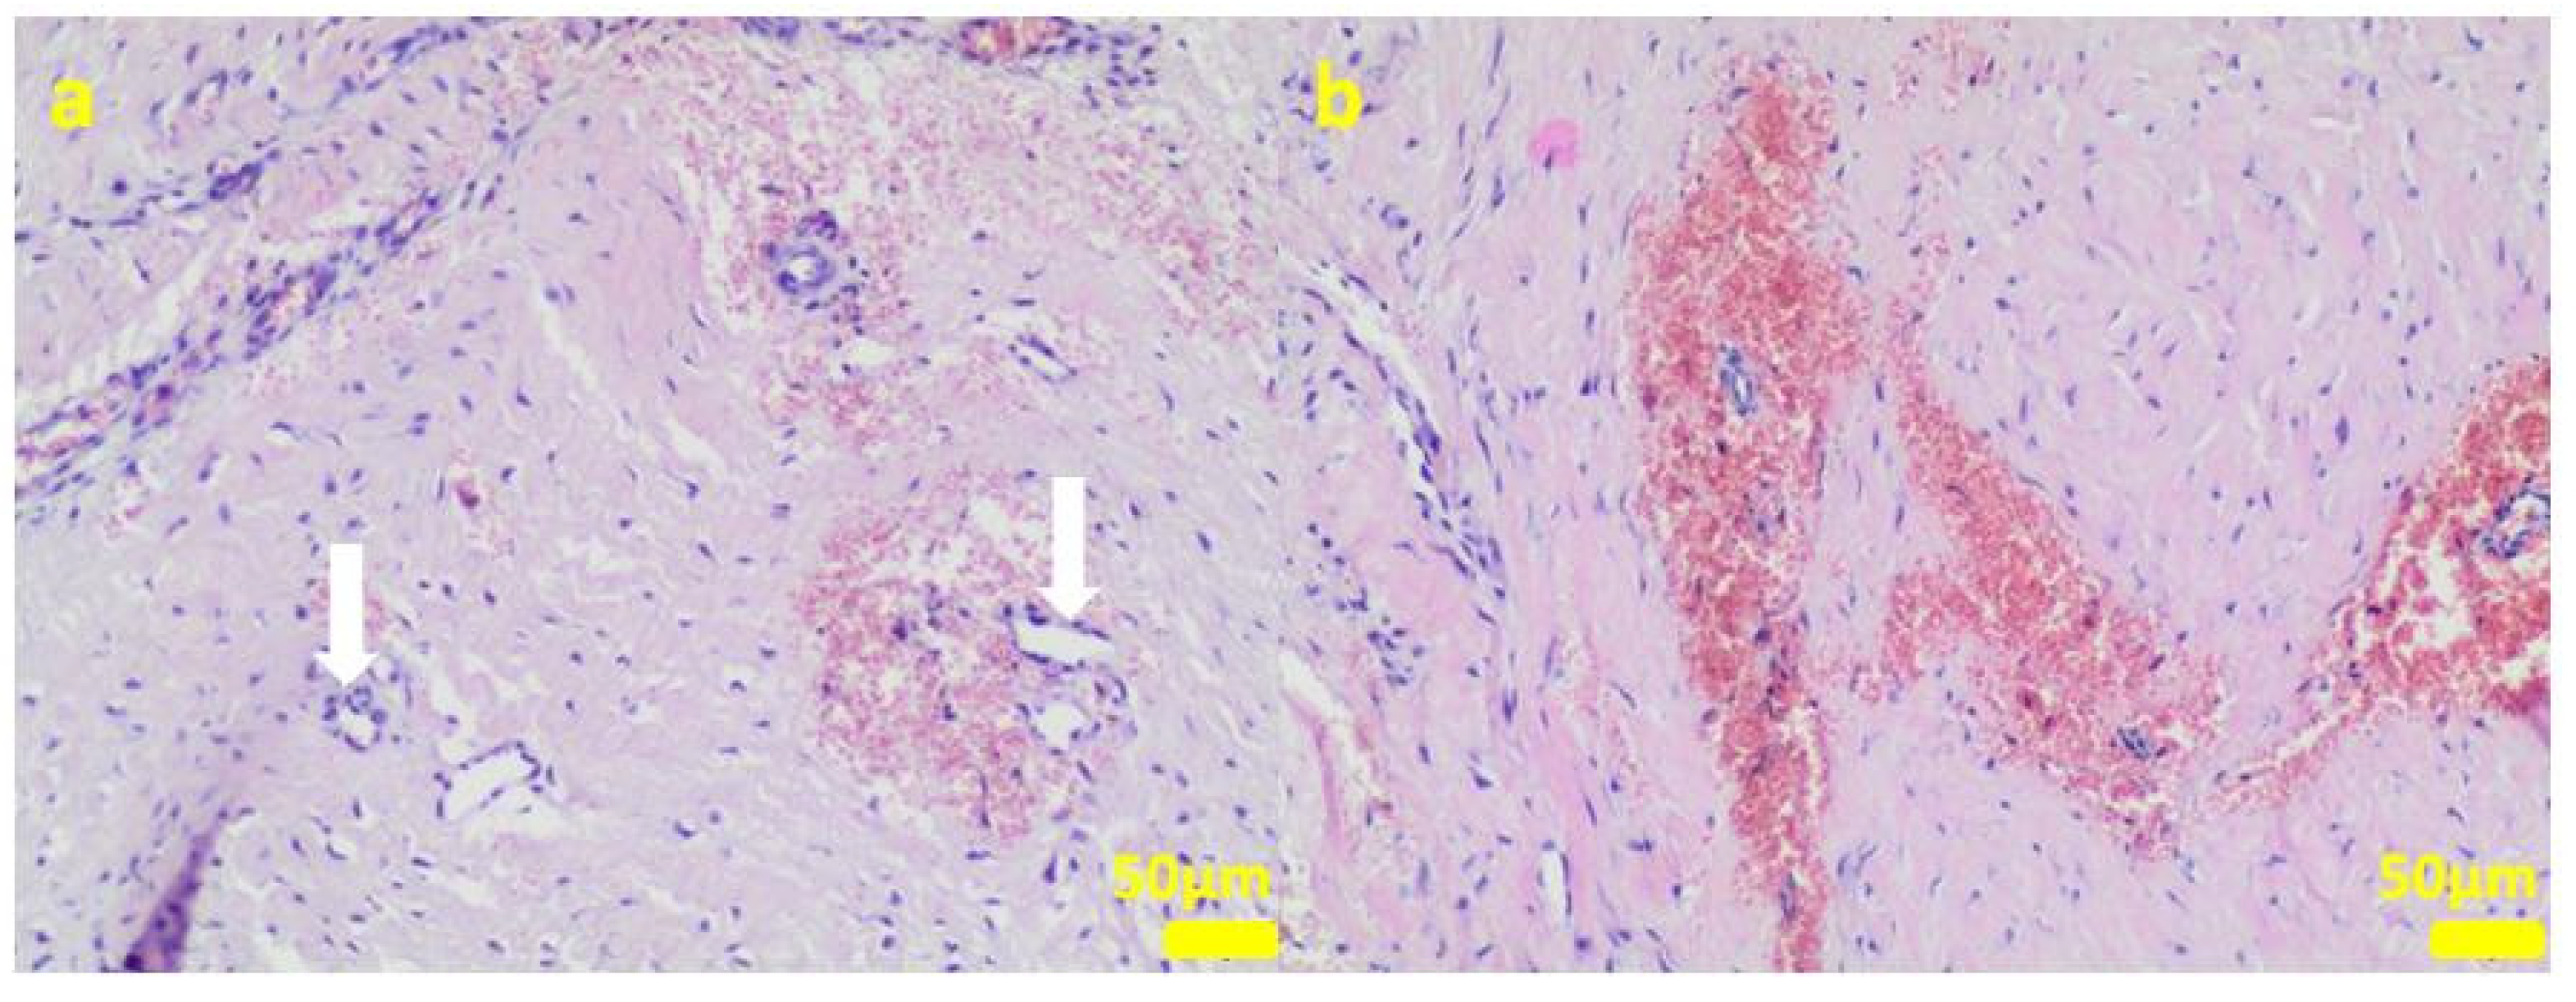

2.1. In Vitro Examinations

2.2. In Vivo Study

4.3. Cell Cultures

4.11. Histopathological Examination